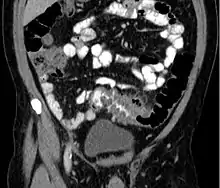

People with the above symptoms are commonly studied with computed tomography, or a CT scan.[15] Ultrasound can provide preliminary investigation for diverticulitis. Amongst the findings that can be seen on ultrasound is non-compressing outpouching of bowel wall, hypoechoic and thickened wall, or there is obstructive fecalith at the bowel wall. Besides, bowel wall oedema with adjacent hyperechoic mesentery can also be seen on ultrasound. However, CT scan is the mainstay of diagnosing diverticulitis and its complications.[9] The diagnosis of acute diverticulitis is made confidently when the involved segment contains diverticula.[16] CT images reveal localized colon wall thickening, with inflammation extending into the fat surrounding the colon.[17] Amongst the complications that can be seen on CT scan are: abscesses, perforation, pylephlebitis, intestinal obstruction, bleeding, and fistula.[9]